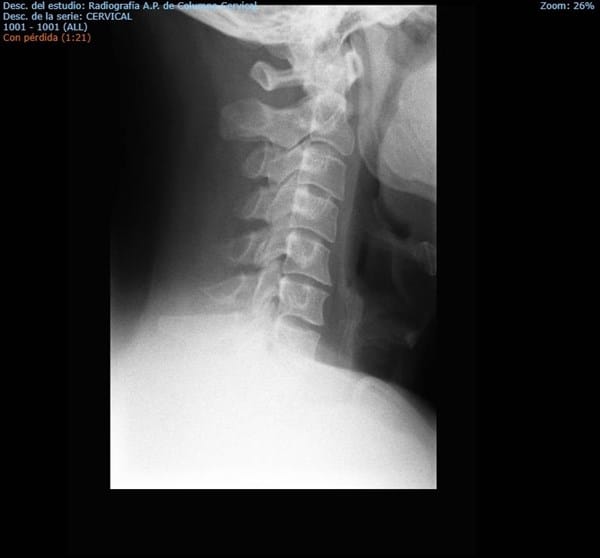

Aquí os coloco unas radiografías de cuello, me las han realizado por constracturas continuas y con dolor intenso.

Me han pedido unas radiografías en base a constracturas muy continuas y de larga duración desde hace como dos años, el asunto es que cada vez son más continuas. Tengo cita con mi médico de cabecera pero con todo este tema de covid van las cosas muy muy lentas.

¿Ustedes ven algo que justifique lo que me ocurre?